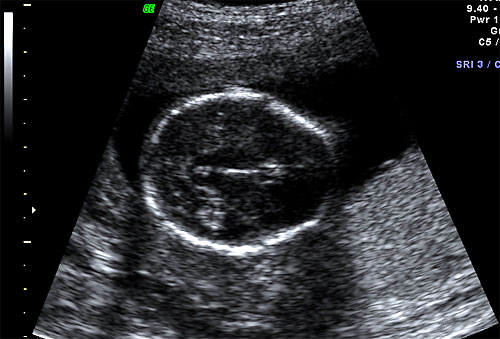

Normal BPD and HC at 16 weeks |

Normal 16 week OFD measurement |